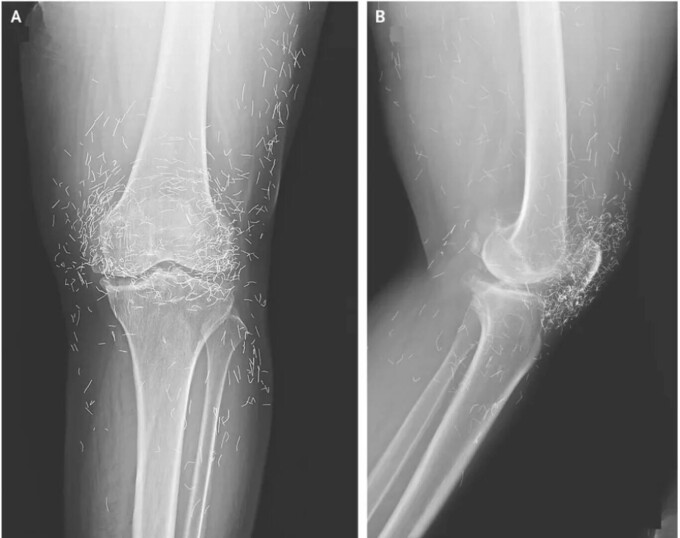

În cele din urmă, a mers la spital pentru că nu mai suporta durerea de genunchi. Radiografiile genunchiului stâng au arătat că tibia din partea interioară a articulației se îngroșase și se întărise. De asemenea, existau excrescențe osoase, numite pinteni, pe porțiunile interioare ale tibiei și ale osului coapsei de lângă articulația genunchiului.

Medicii au mai observat însă și altceva: sute de pete pe radiografie în jurul articulației genunchiului, care s-au dovedit a fi fire minuscule de aur.

Ulterior, doctorii au aflat că firele fuseseră introduse ca parte a tratamentelor de acupunctură ale femeii. Aceste fire scurte, sterile, de aur au fost lăsate intenționat în țesut pentru a oferi o stimulare continuă.

În raportul lor despre cazul genunchiului, medicii au remarcat că firele de aur introduse în timpul acupuncturii pot îngreuna citirea radiografiilor.